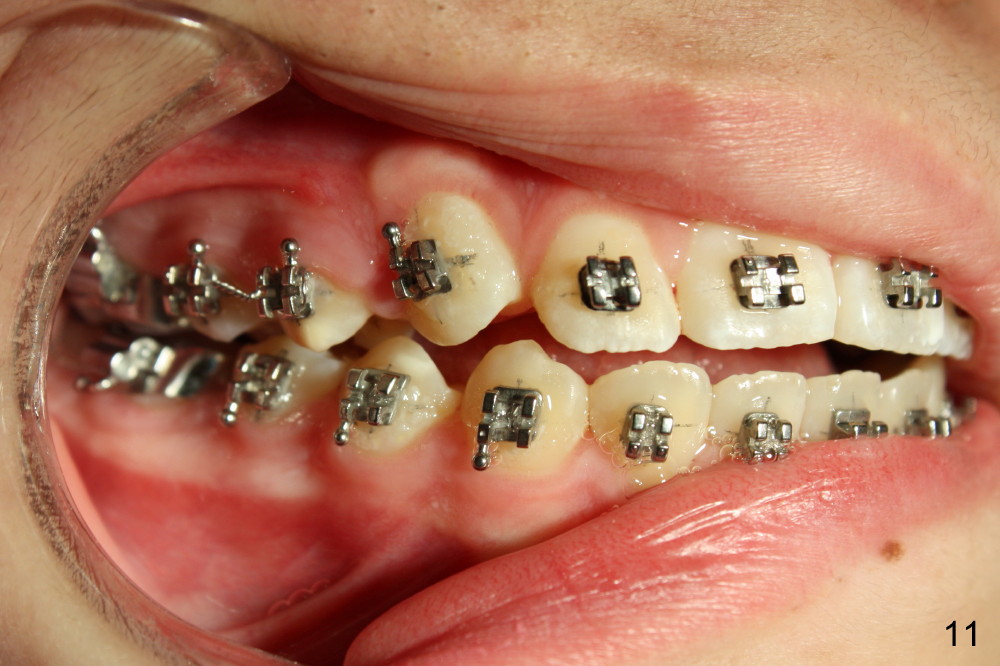

The canines are continually erupting 3 months of elastics (Fig.11,12). A flexible wire (.0175' twisted wire) is installed for the upper arch for further orthodontically-assisted eruption (Fig.12).